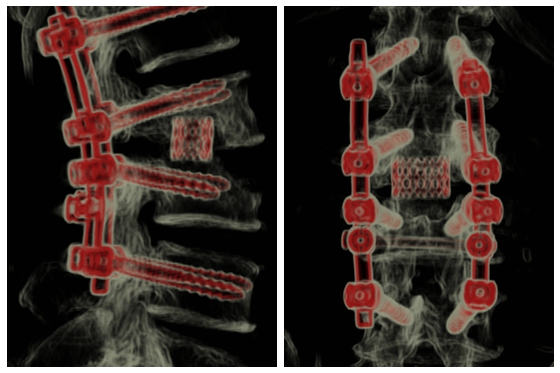

术后三维CT图

面对这一棘手手术病例,由中南大学湘雅医院脊柱外科吴天定副教授领衔,经过多学科团队严谨论证,决定采用一期后路病灶清除+稳定性重建的创新术式,在彻底清除病灶的同时实现脊柱稳定。手术通过单一后路切口完成结核脓肿清除、坏死椎间盘切除及椎管减压。针对患者骨质缺损严重的椎间隙,创新性植入生物相容性优良的钛笼,结合自体骨与异体骨复合植骨技术,为脊柱重建提供双重保障,在彻底清除病灶的同时最大程度保护脊髓神经功能。术后患者腰腿痛症状明显缓解,术后3天即可佩戴支具下床活动,恢复效果显著,目前患者已康复出院。